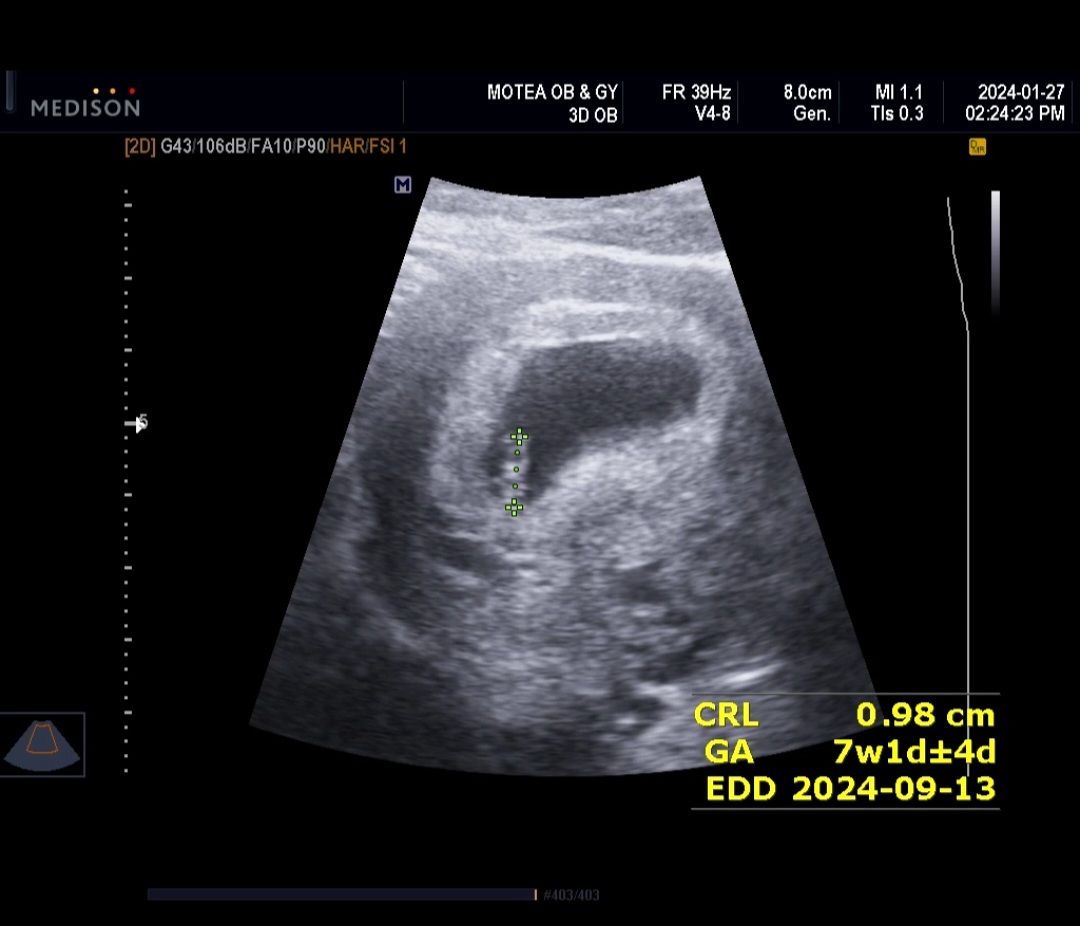

7주1 or 2일 쵸음파 스크린샷

오늘 배아가 1cm에 심박수 130 이 되어야한다구 하더라구요! 오늘 차수로 0.97~8cm, 140 보고왔습니다. :) 2주뒤에 가면 2cm에 심박수 160이 되어야 한대요. 병원가면 시험보는 느낌이네요~~ 안그래도 어렵게 시험관 5번에 얻은애기라..ㅎㅎ 우리모두 만출해요!!!